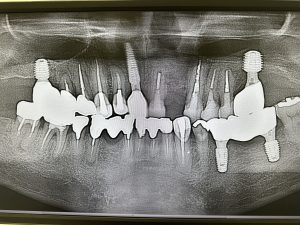

画像は全てメタルプレート、クリアランスが少ない

これで6本目

内容が7140!🤪感染根管病巣大の症例が多くて背中が痛い😭